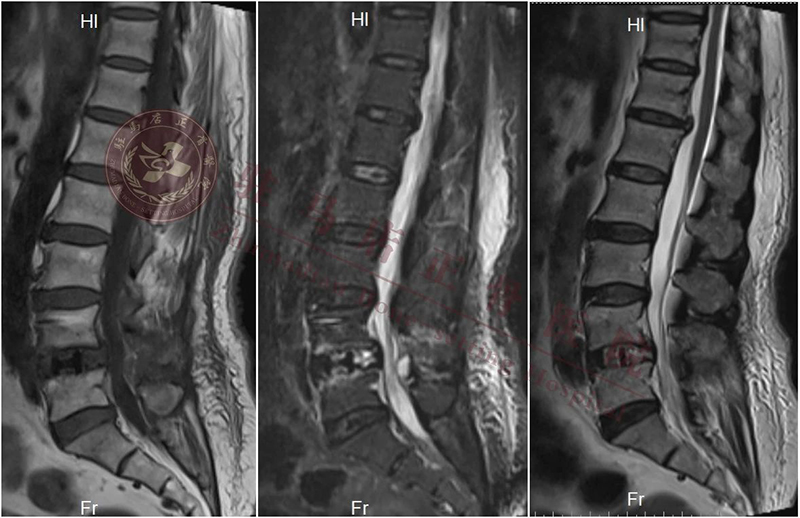

【诊 断】:1.腰椎管狭窄症(L4/L5); 2.腰椎间盘突出症(L4/L5); 3.腰4椎体滑脱(II度)

【术前计划】:通过影像等相关检查,明确诊断,根据诊断确定手术方式:经内镜下行腰4/5椎间盘切除、椎管扩大减压、椎间植骨融合复位、经皮椎弓根螺钉单侧内固定术

{ 术前 }

术后影像